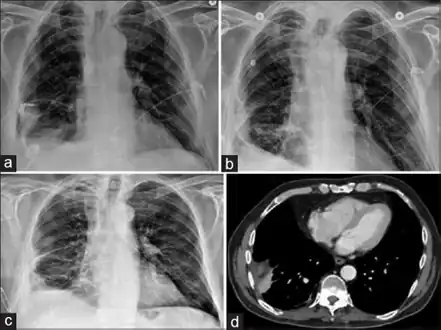

Lungs

Empyema

Empyema with abscess